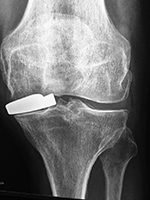

Unicompartmental knee prosthesis placed in the medial compartment (AP view) Unicompartmental knee prosthesis placed in the medial compartment (lateral view) Unicompartmental knee prosthesis placed in lateral knee compartment

Unicompartmental knee prosthesis - AP view Lateral unicompartmental knee prosthesis Lateral unicompartmental knee prosthesis

From Taljanovic, 2005 50 year-old man with lateral knee compartment degenerative osteoarthritis